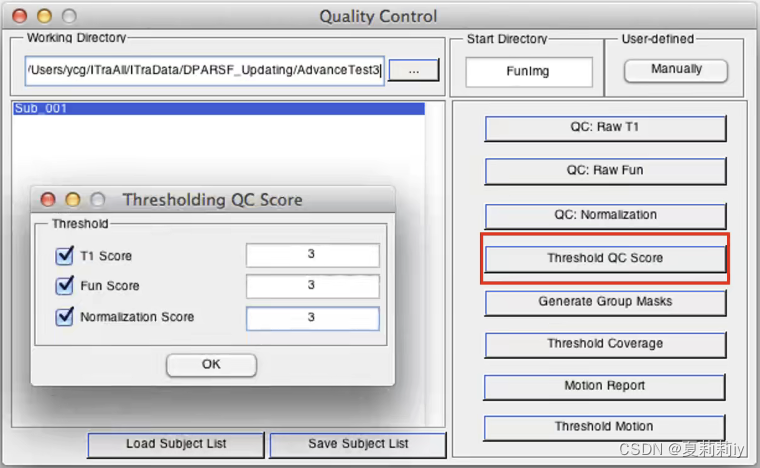

(5)Threshold QC Score

①这个设定得到是分数的下界,所得数据要大于这分数才能进入被统计分析数据

②设定完后左边框中小于这些分数的被试都会被排除掉